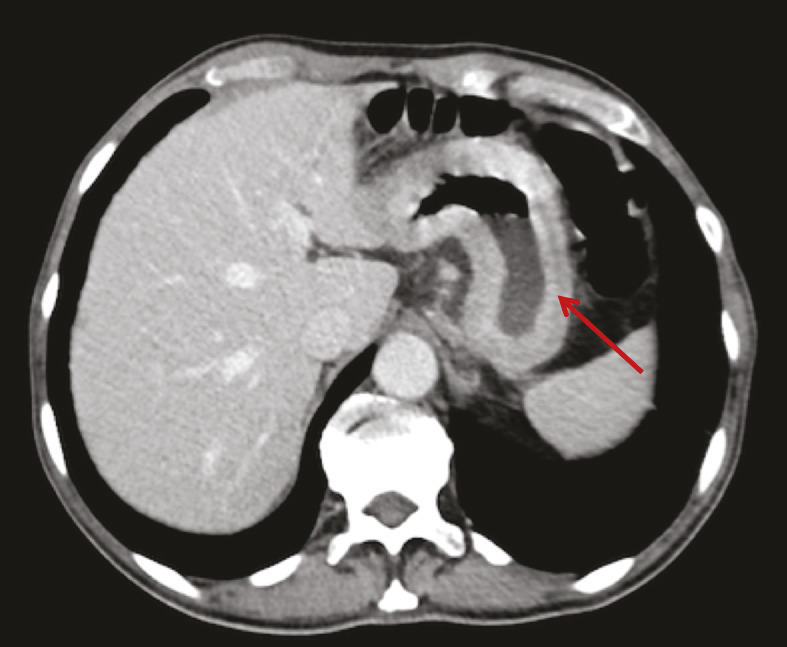

Un mois et demi plus tard, devant la persistance des symptômes et la perte de 6 kg supplémentaires, une tomodensitométrie est réalisée, qui montre un aspect épaissi de la paroi gastrique mesurant 17 mm d’épaisseur, limité à l’antre gastrique. Une nouvelle endoscopie œsogastroduodénale est alors réalisée, qui ne note pas d’anomalie évidente, si ce n’est toujours un aspect rigide à l’insufflation. Une écho-endoscopie haute est réalisée, qui révèle un épaississement localisé de la paroi gastrique et permet des biopsies guidées qui décè- lent la présence d’un adénocarcinome gastrique avec présence de cellules indépendantes.

Il faut savoir répéter l’exploration endoscopique en cas de persistance de symptômes dyspeptiques et de signes d’alarme. En effet, si la sensibilité de l’endoscopie pour les adénocarcinomes de type lieberkühnien est excellente, elle est moins bonne dans les linites gastriques qui peuvent être ignorées. De plus, les biopsies sont volontiers négatives dans les linites, avec une sensibilité de 50 % uniquement,1 incitant à réaliser des biopsies multiples (minimum 8) en cas de suspicion de cancer, et éventuellement des biopsies en puits, des macrobiopsies ou surtout une ponction-biopsie guidée par l’échoendoscopie.

De même, une confusion fréquente est faite entre le type histologique ADCI et la linite gastrique. Cette dernière est définie macroscopiquement, en anatomopathologie, en endoscopie (fig. 2) ou en imagerie (fig. 3), par un aspect épaissi et rigide de la paroi gastrique. L’aspect de linite est fréquemment associé au type histologique ADCI, comme cela a été noté dans une série de 27 linites gastriques analysées par deux anatomopathologistes différents. P armi ces linites, 21 étaient des adénocarcinomes gastriques à cellules indépendantes et 6 d’autres types histologiques selon la classification de l’OMS. Après une troisième lecture des lames, il apparaissait que 4 tumeurs avaient un contingent minoritaire de cellules isolées (< 50 %) et 2 tumeurs étaient des adénocarcinomes tubulaires.3